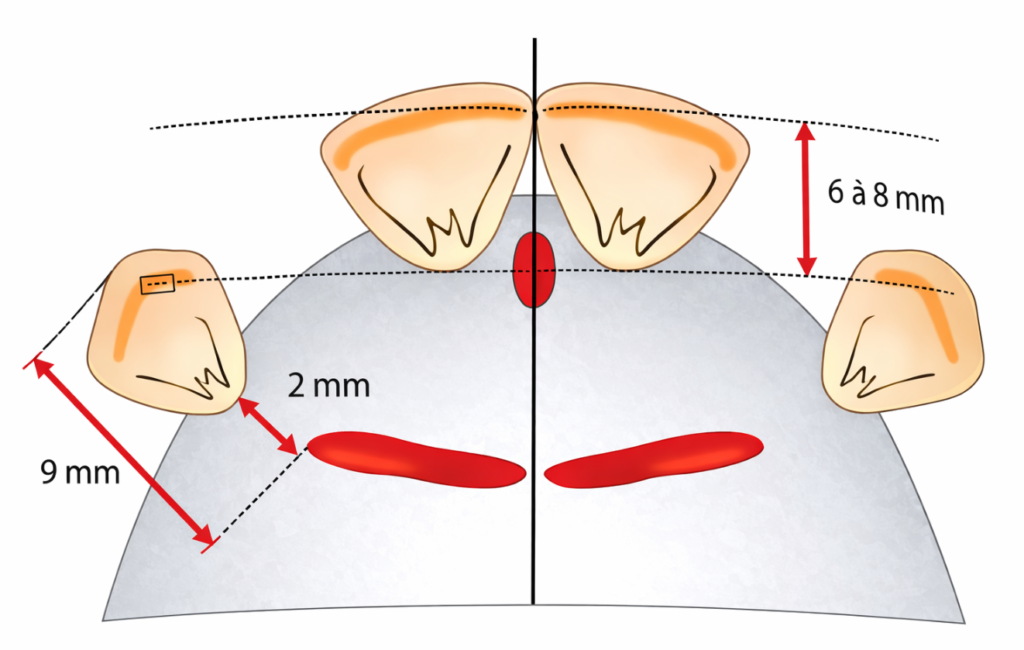

L’incisive centrale supérieure

Plan horizontal :

Le bord libre se situe à environ 6 à 8 mm en avant de la papille rétro-incisive.

Plan frontal :

Les deux incisives centrales se situent de part et d’autre de la ligne médiane, leur grand axe est parallèle à cette ligne. Le bord libre est en contact avec le plan d’occlusion.

L’incisive latérale supérieure

Plan horizontal :

Son bord libre suit la courbe amorcée par l’incisive centrale, il peut être légèrement en retrait.

Plan frontal :

La canine supérieure

Plan horizontal :

Les pointes des deux canines sont reliées par une droite qui passe par le centre de la papille rétro-incisive.

Plan frontal :

L’axe de la canine est droit, parallèle à celui de l’incisive centrale supérieure. La pointe de la canine est en contact avec le plan d’occlusion.